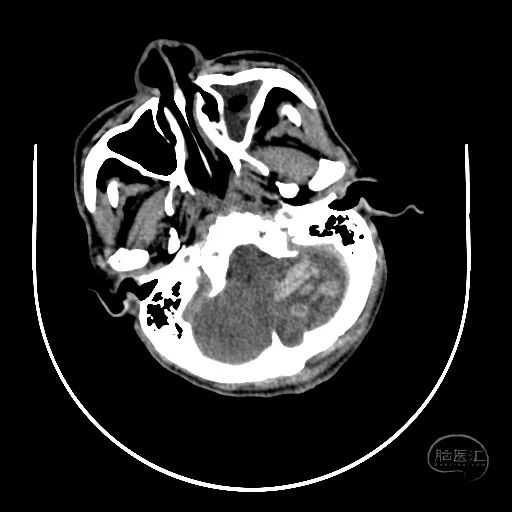

颅脑CT可见左侧小脑半球挫裂伤,第四脑室明显受压。

右额叶脑挫裂伤并血肿,侧脑室额角受压,脑室无明显扩张。

中线结构稍向左侧偏移。

骨窗显示枕骨粉碎性骨折,累及枕骨大孔左侧,齿突尚居中。